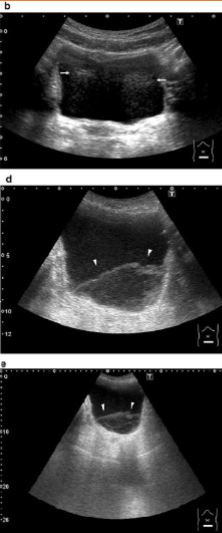

Enhancement

Caused by a structure of low attenuation adjacent to a structure of normal attenuation

Appears as a band of increased echogenicity behind an area of low attenuation

Reduced by:

Gain & TGCs

Spatial compounding

Can be diagnostically useful to distinguish fluid-filled from solid objects

Fluid filled objects have this artifact

Solid objects DO NOT have this artifact

Posterior Acoustic Enhancement, low, normal, increased, attenuation, Gain, TGCs, Spatial compounding, Fluid-filled, Solid

AKA ___ ___ ___

Caused by a structure of ___ attenuation adjacent to a structure of ___ attenuation

Appears as a band of ___ echogenicity behind an area of low ___

___ & ___

___ ___

___ objects have enhancement

___ objects DO NOT have enhancement